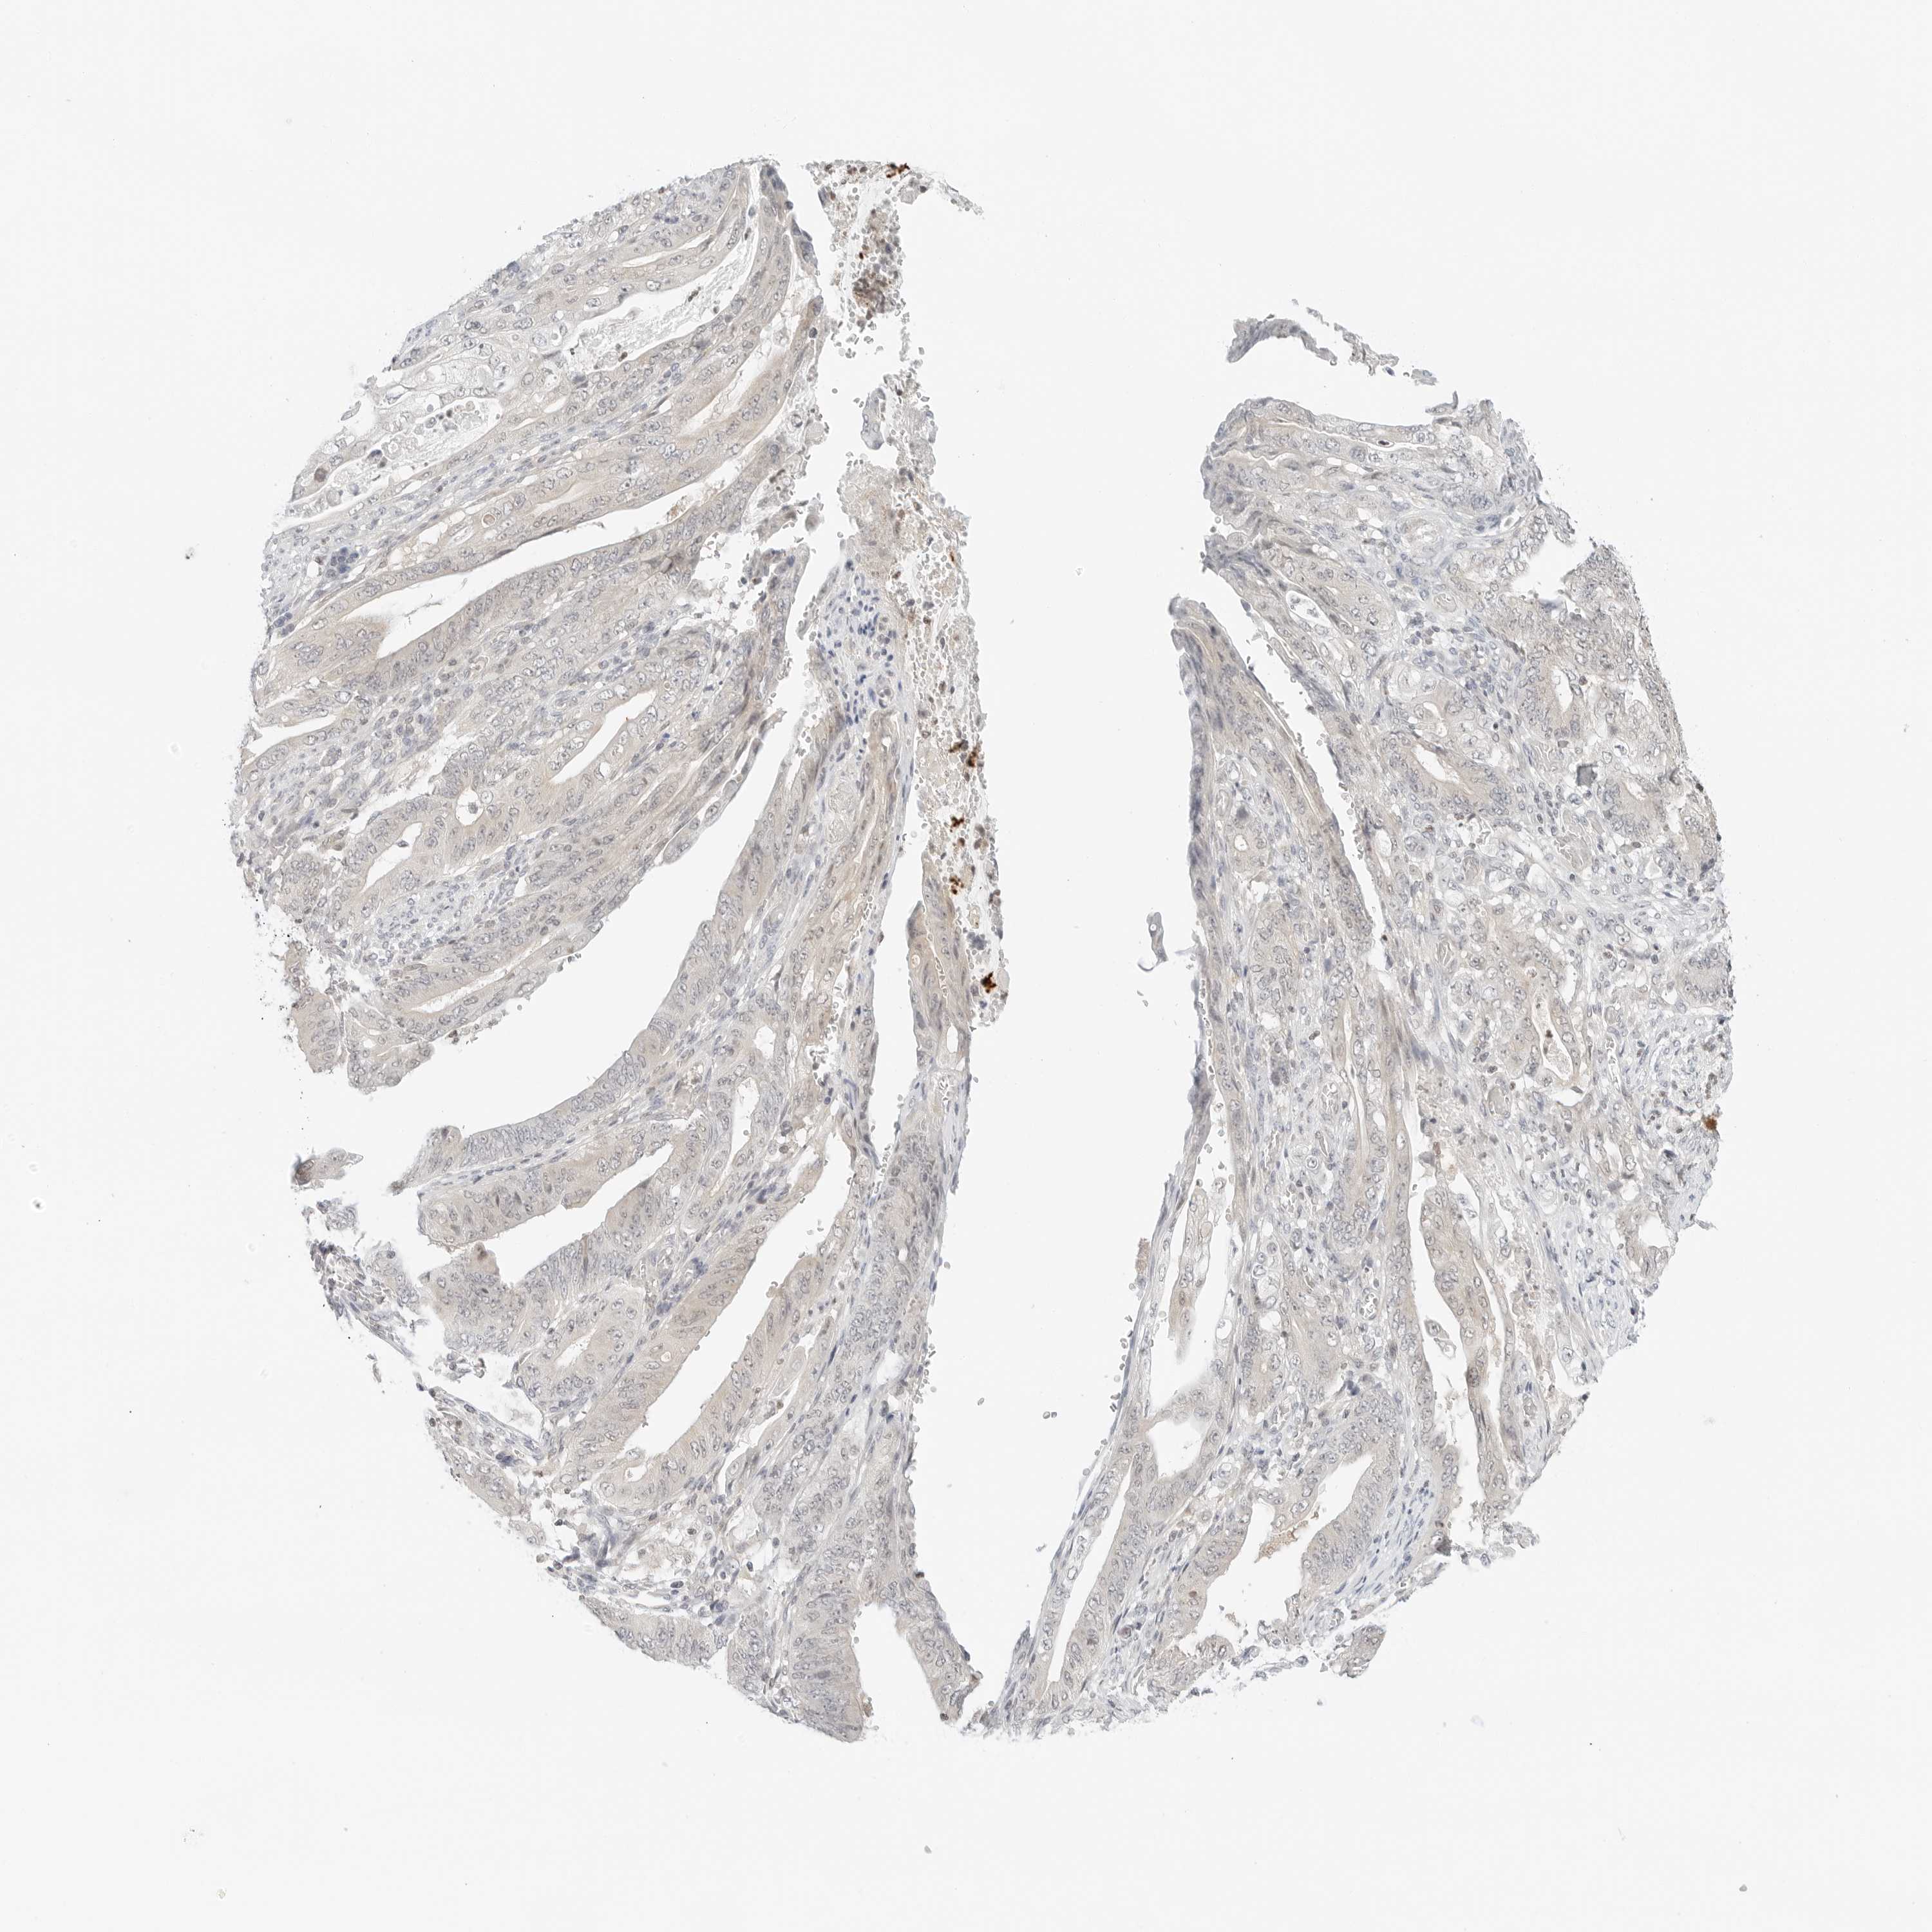

STOMACH CANCER - Protein expressioni

A mouse-over function shows sample information and annotation data. Click on an image to view it in a full screen mode. Samples can be filtered based on level of antibody staining by selecting one or several of the following categories: high, medium, low and not detected. The assay and annotation is described here.

Note that samples used for immunohistochemistry by the Human Protein Atlas do not correspond to samples in the TCGA dataset.

Antibody stainingi

Antibody staining in the annotated cell types in the current human tissue is reported as not detected, low, medium, or high, based on conventional immunohistochemistry profiling in selected tissues. This score is based on the combination of the staining intensity and fraction of stained cells.

Each image is clickable and will lead to virtual microscopy that enables deeper exploration of all samples and also displays staining intensity scores, fraction scores and subcellular localization as well as patient and tissue information for each sample.

Antibody HPA028602

Antibody HPA028686

Staining

High

Medium

Low

Not detected

Intensity

Strong

Moderate

Weak

Negative

Quantity

>75%

75%-25%

<25%

None

Location

Nuclear

Cytoplasmic/membranous

Cytoplasmic/membranous,nuclear

Adenocarcinoma, NOS